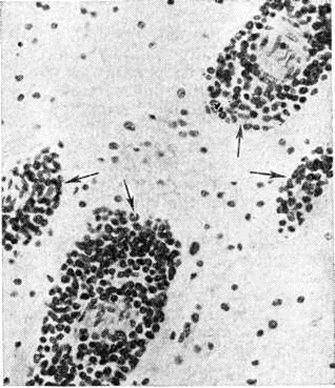

Острый миелобластный лейкоз в развёрнутой стадии болезни характеризуется выраженной лейкозной инфильтрацией костного мозга и других органов. В печени лейкозные разрастания локализуются в синусоидных капиллярах и в области портальных трактов. Аналогичное расположение инфильтратов имеется и при других более редких формах острого Лейкозы (монобластном, миеломонобластном, недифференцируемом, промиелоцитарном и другие), поэтому данный признак не может служить основанием для разграничения форм острого Лейкозы В лёгких лейкозная инфильтрация обычно выявляется по ходу межальвеолярных перегородок с выходом бластных клеток в просветы альвеол (рисунок 3), возможна локализация и в окружности бронхов, сосудов, междольковых перегородках. У детей при этой форме Лейкозы лейкозные разрастания в вилочковой железе располагаются в соединительнотканных прослойках, сдавливают дольки, что сопровождается увеличением количества аргирофильных волокон. У взрослых типично развитие множественных узлов в надкостнице плоских и трубчатых костей, почках, печени, половых железах, жировой клетчатке (подкожной, ретробульбарной, клетчатке большого сальника и малого таза), иногда в коже, конъюнктиве, твёрдой мозговой оболочке и костном мозге. В ряде случаев в области опухолевых узлов и системных поражений имеется зелёное окрашивание ткани (хлоролейкоз). Аналогичные изменения могут выявляться и при Лейкозы у детей.